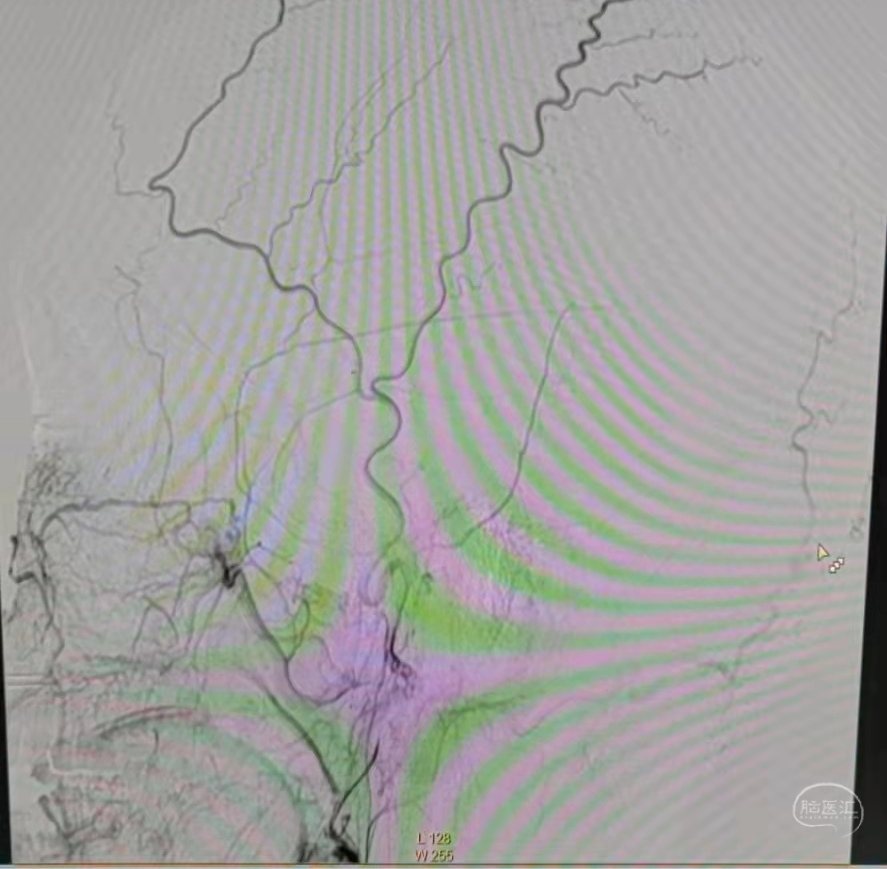

荧光造影示:吻合桥动脉通畅。

荧光造影示:吻合桥动脉通畅。

荧光造影示:吻合桥动脉通畅。

荧光造影示:吻合桥动脉通畅。

荧光造影示:吻合桥动脉通畅。